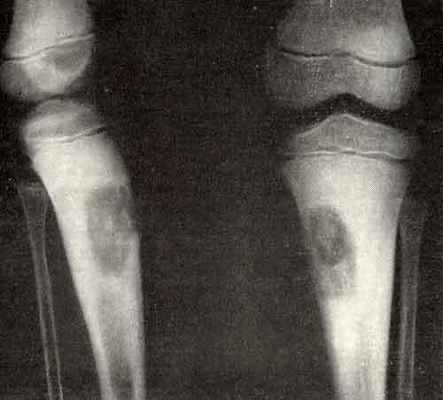

Фиброма костей характеризуется очаговой резорбцией (рассасыванием) кортикального слоя отдела трубчатой кости с замещением его на фиброзную. Образуется в бедренной, берцовой, плечевой и пяточной костях. Чаще всего встречается у детей и подростков. Во многих случаях приводит к патологическим переломам.

- хондромиксоидная фиброма – редкая хрящеобразующия опухоль;

- десмопластическая фиброма – редкая локально агрессивная внутрикостная опухоль;

- неоссифицирующая фиброма – доброкачественный фиброзный дефект костной ткани;

- десмоидная фибриома – редко встречается, происходит из избытка волокон коллагена и дифференцированных фибробластов, часто прогрессирует и рецидивирует. Образуются в мягких тканях, забрюшинном пространстве или на брюшной стенке. Распространенные места для таких опухолей – шрамы от кесарева сечения или операций;хондриомиксомы – редкие опухоли, которые поражают костную ткань – края трубчатых костей, таз, ребра, позвонки, стопы, плюсну;

Неостеогенные опухоли образуются в бедренной кости и провоцируют разрушение трубчатых костей скелета. В запущенной стадии заболевание становится причиной патологического перелома кости. Редко (3–5% клинически диагностируемых случаев) новообразование уменьшается в размерах без хирургического вмешательства. Другие виды костных опухолей отличаются агрессивным ростом. Так, десмопластическая фиброма способна увеличиться в объеме вдвое за 2–3 недели.